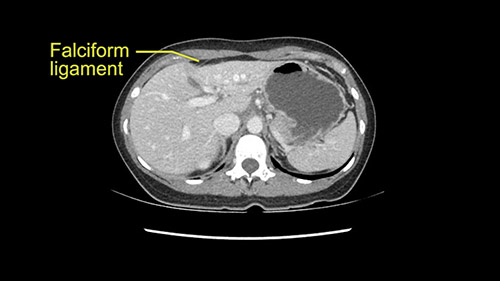

So if we look at the CT scan, on the axial, it’s a larger lesion. It’s about 6 or 7 or 8 centimeters. So it does look a bit threatening in terms of its resectability but if you really drill down deeply into the anatomy, and I think the coronal [imaging] is even better, you can see that the entire mass is on the patient’s left side of the falciform ligament. So it’s really only a left-sided tumor and not even really a left-sided tumor because Segment 4 is uninvolved anatomically.

Otherwise, the dissection at the porta is on the left side of the falciform [ligament] so we don’t worry too much about any of the other major structures. This is really an operation more of avoidance by staying far into the periphery as opposed to worrying about the porta. So we prepared her for surgery and she consented and was anxious to proceed.

As I review the CT scan, we have both arterial and venous phases, the tumor is obvious. But I’ll start by saying that the liver itself does not appear to be cirrhotic to my eye. It’s got a normal contour and allied to that, that I do not see evidence of portal hypertension. The spleen is normal, there’s no collateral vessels. The tumor itself, I measured maximally at about 11 centimetres in diameter and I’m told the alpha fetoprotein is very high (over 10000), which is entirely consistent with this being a solitary hepatocellular carcinoma that is very exophytic. It seems to emanate off the inferior margin of Segment 3 (because that’s the falciform). I’ll start by saying that this is not transplantable. The tumor exceeds our guidelines for transplantation, but it's likely resectable based on normal liver and no portal hypertension.

So the issue with regards to resection. A left sided tumor. I believe I can see the falciform ligament right here so we’re looking at a resection of Segments 2, 3 of the left lobe of the liver. The left portal vein is right there. I think we’ll be wiser to take the left portal vein and therefore get well into Segment 4 and do a left hemihepatectomy. Certainly, one does not need to take the middle hepatic vein; it’s miles from the tumor.

The tumor is so close to the falciform ligament, I had a question mark about the Segment 4b relation between segment 4b and segment 3. In a normal resection of segment 2 and 3, we would be keeping on the left side of the falciform ligament and start getting segment 3 and 2 portal pedicles but in here its getting so close. So oncologically, 4b should be checked during the OR.